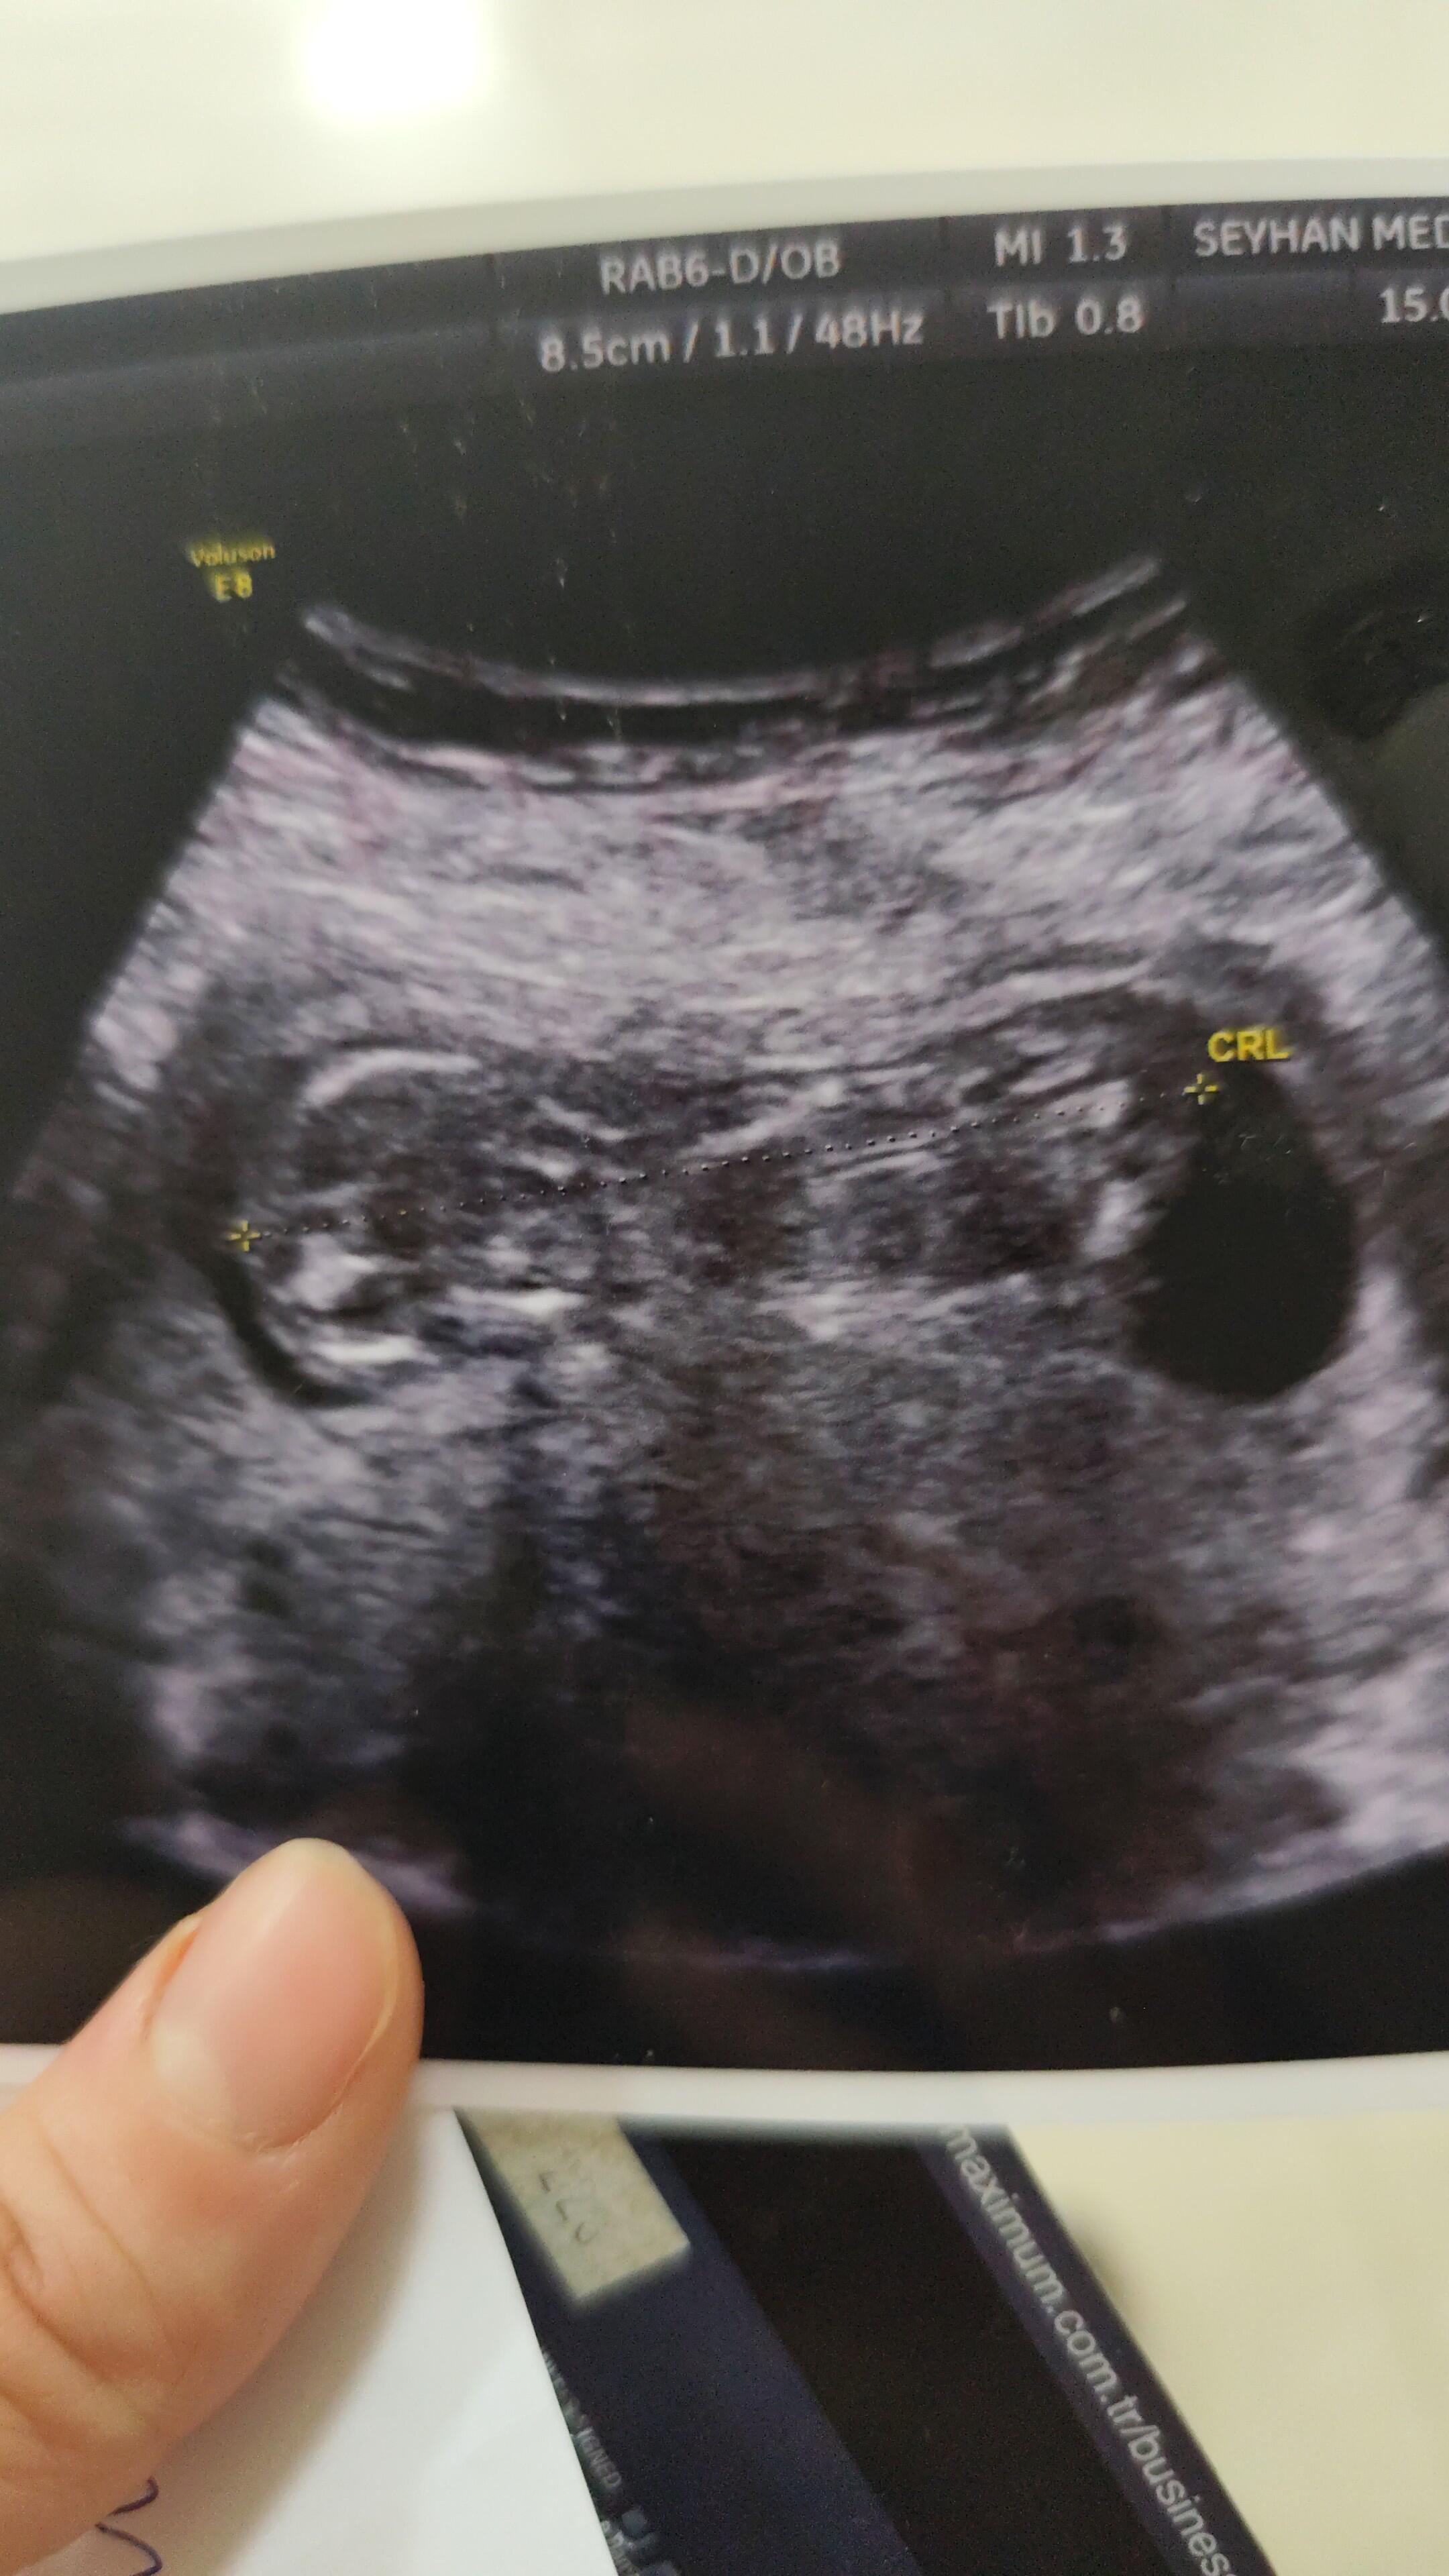

Ben benim çocugun iki defadır alamıyorum çünkü hep sırtını dönüp bacagını kapatıyor şuan 14 haftalıgız göremedi henüz

varsa tahminler albilirim ![]()

Bacak arası fazla gözükmüyor birde çok net değil ama duruş kız bebek gibi canım farklı net fotoğrafi var mı tekrar at bakayım

Baktım canım ama net fotoğraf atarsa tekrar bakarım

Kese şekli duruşu erkek bebek gibi ama sonraki attığına bir daha baktım kız gibi başka net var mı canım senin ki sürpriz bebek çözemedim ![]()